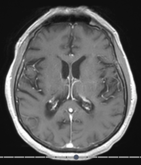

Standardized body region labelling of individual images provides data that can improve human and computer use of medical images. A CNN-based classifier was developed to identify body regions in CT and MRI. 17 CT (18 MRI) body regions covering the entire human body were defined for the classification task. Three retrospective databases were built for the AI model training, validation, and testing, with a balanced distribution of studies per body region. The test databases originated from a different healthcare network. Accuracy, recall and precision of the classifier was evaluated for patient age, patient gender, institution, scanner manufacturer, contrast, slice thickness, MRI sequence, and CT kernel. The data included a retrospective cohort of 2,934 anonymized CT cases (training: 1,804 studies, validation: 602 studies, test: 528 studies) and 3,185 anonymized MRI cases (training: 1,911 studies, validation: 636 studies, test: 638 studies). 27 institutions from primary care hospitals, community hospitals and imaging centers contributed to the test datasets. The data included cases of all genders in equal proportions and subjects aged from a few months old to +90 years old. An image-level prediction accuracy of 91.9% (90.2 - 92.1) for CT, and 94.2% (92.0 - 95.6) for MRI was achieved. The classification results were robust across all body regions and confounding factors. Due to limited data, performance results for subjects under 10 years-old could not be reliably evaluated. We show that deep learning models can classify CT and MRI images by body region including lower and upper extremities with high accuracy.

翻译:个人图像标准化体格标签提供了可以改进人体和计算机医疗图像使用的数据; 开发了一个CNN的分类器,以确定CT和MRI的人体区域; 为分类任务确定了覆盖整个人体的17个CT(18MRI)机构区域; 为AI模型培训、验证和测试建立了三个追溯数据库,每个机构区域的研究分布均衡; 测试数据库来自不同的保健网络; 对病人年龄、病人性别、机构、扫描机制造商、对比、切片厚度、MRI序列和CT内核的分类器进行了准确、回顾和精确性评价; 数据包括2 934个匿名CT案例的追溯组(培训:1 804项研究、验证:602项研究、测试:528项研究)和3 185个匿名MRI案例(培训:1 911项研究、验证:636项研究、测试:638项研究)。 初级护理医院、社区医院和成像中心27个机构对测试数据集进行了准确性评估; 数据包括:92%以上的性别比例和科目的追溯性案例; 95年的高级和90个高等级数据序列,显示为91至90区域。